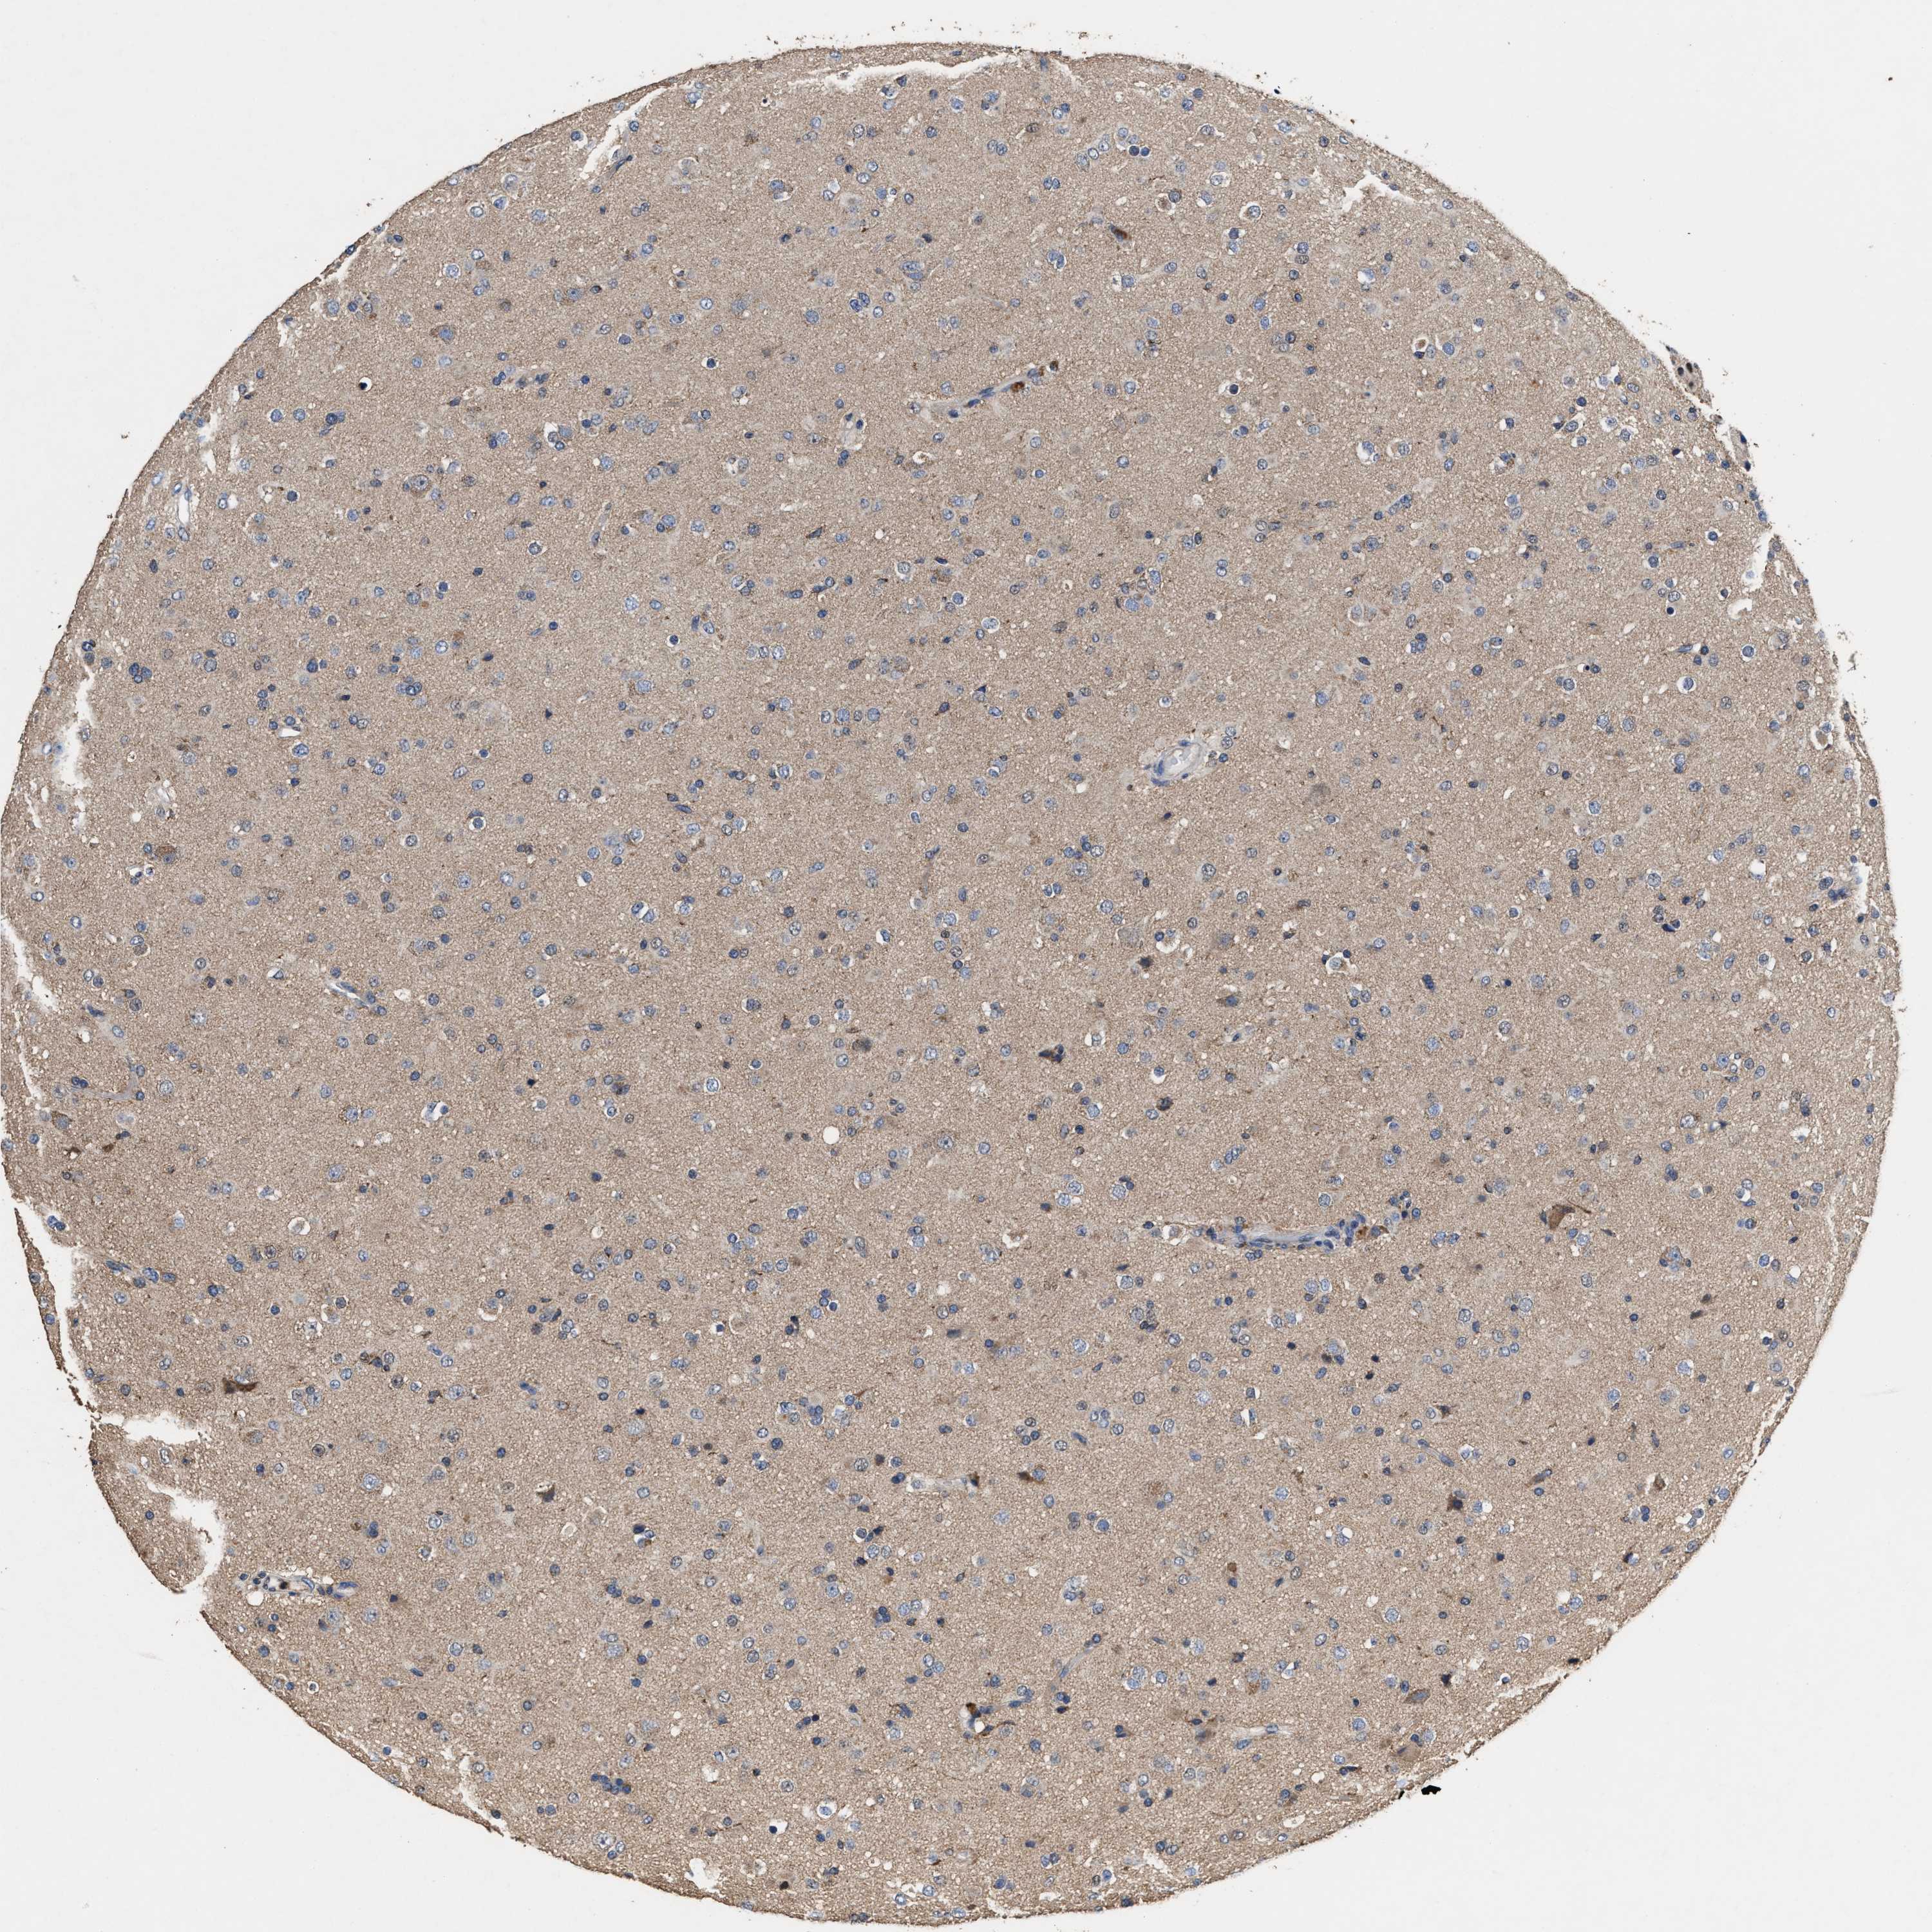

GLIOMA - Protein expressioni

A mouse-over function shows sample information and annotation data. Click on an image to view it in a full screen mode. Samples can be filtered based on level of antibody staining by selecting one or several of the following categories: high, medium, low and not detected. The assay and annotation is described here.

Note that samples used for immunohistochemistry by the Human Protein Atlas do not correspond to samples in the TCGA dataset.

Antibody stainingi

Antibody staining in the annotated cell types in the current human tissue is reported as not detected, low, medium, or high, based on conventional immunohistochemistry profiling in selected tissues. This score is based on the combination of the staining intensity and fraction of stained cells.

Each image is clickable and will lead to virtual microscopy that enables deeper exploration of all samples and also displays staining intensity scores, fraction scores and subcellular localization as well as patient and tissue information for each sample.

HPA022434

HPA022953

HPA022959

HPA028758

CAB007783

Glioma, malignant, High grade

Glioma, malignant, Low grade

Glioblastoma, NOS